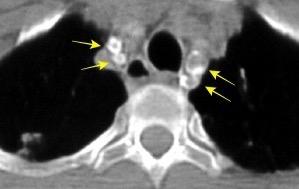

Silicosis secundaria al pulido con chorro de arena. Tejidos ”Denim”. (vaqueros, etc.)

Marchiori E et al. Conglomerated masses of silicosis in sandblasters: High-resolution CT findings. Eur Radiol 2006

Alper F,, et al. CT findings in silicosis due to denim sandblasting. Eur Radiol. 2008